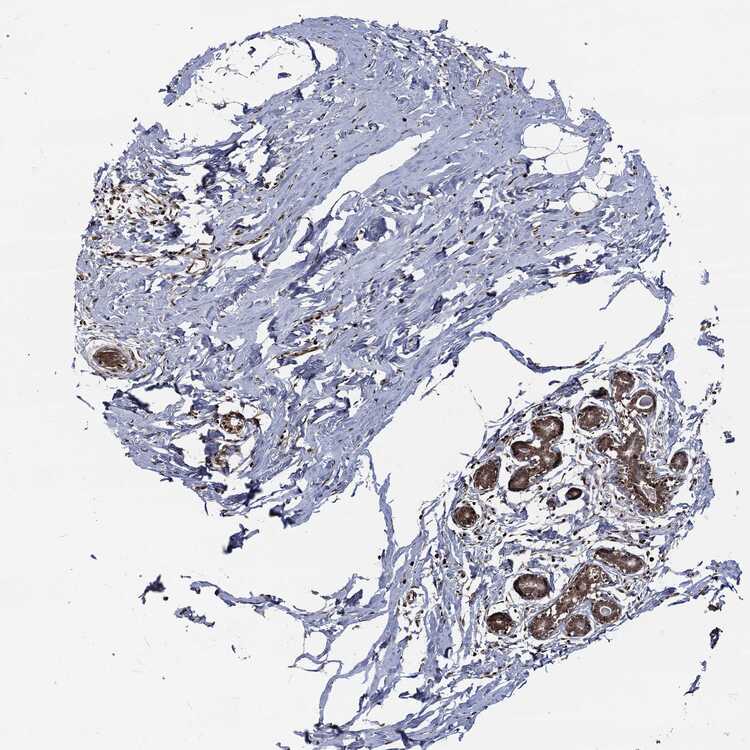

BREAST - Antibody stainingi

Antibody staining in the annotated cell types in the current human tissue is reported as not detected, low, medium, or high, based on conventional immunohistochemistry profiling in selected tissues. This score is based on the combination of the staining intensity and fraction of stained cells.

Each image is clickable and will lead to virtual microscopy that enables deeper exploration of all samples and also displays staining intensity scores, fraction scores and subcellular localization as well as patient and tissue information for each sample.

Antibody HPA069985Antibody CAB005883Antibody CAB078687Antibody CAB080398

Adipocytes HighNot detectedNot detectedHigh

Glandular cells HighHighNot detectedMedium

Myoepithelial cells MediumHighNot detectedMedium